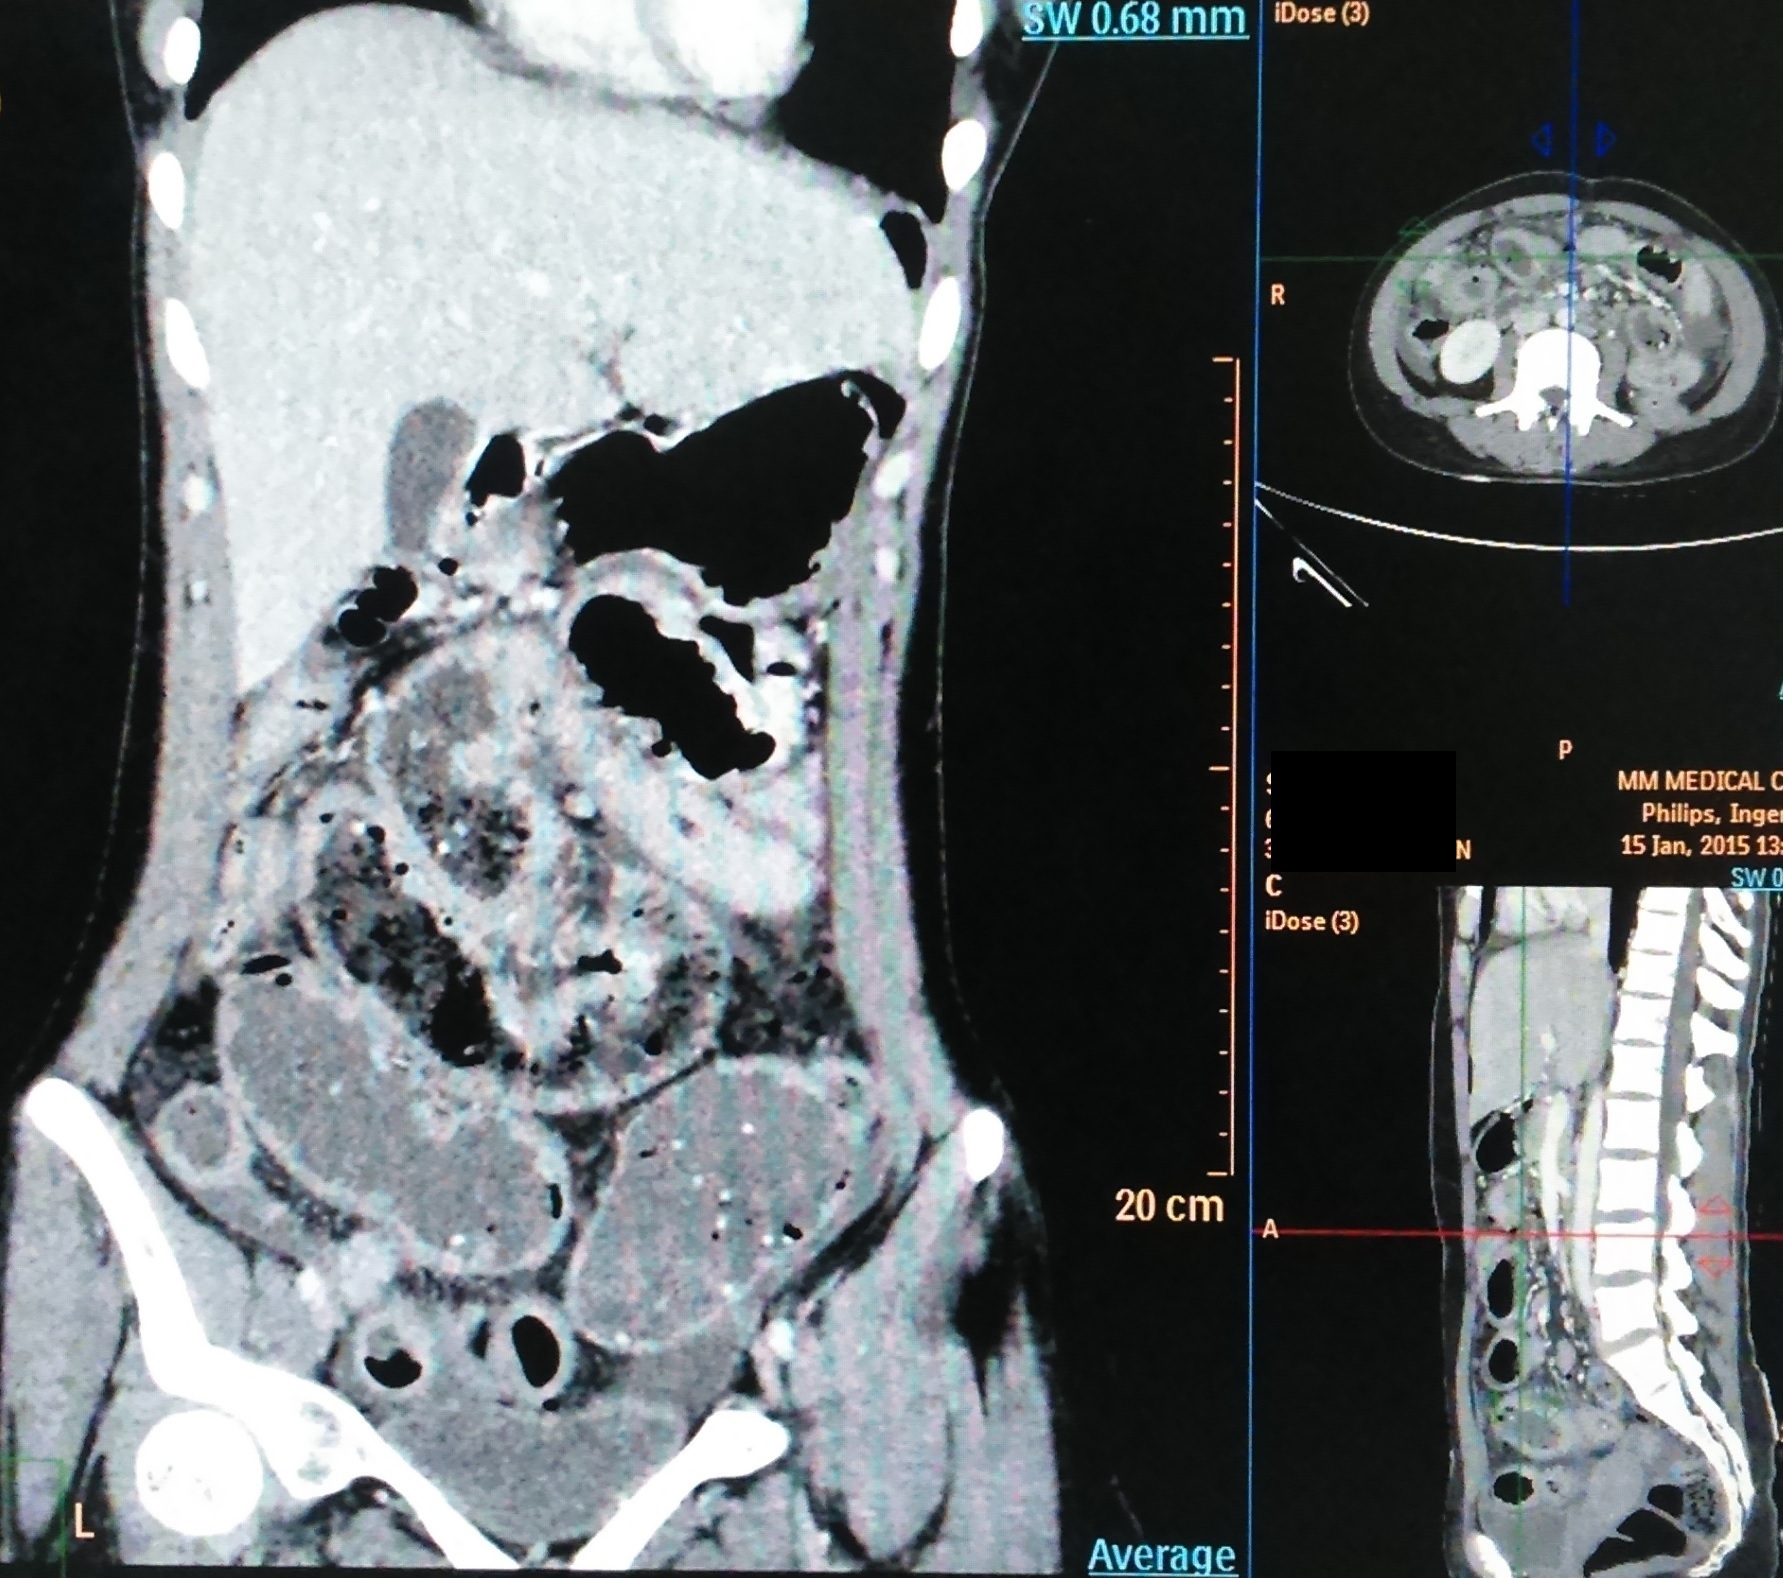

Material and methods. This study was carried out at M.M. Institute of Medical Sciences and Research, Mullana, Ambala, India between April 2013 – March 2016 in the Department of Pediatric Surgery. This is a prospective study. A total of 17 patients diagnosed with abdominal cocoon secondary to tuberculosis have been included in the study.

Results. A total of 17 patients presented to the emergency ward with features of acute intestinal obstruction. The average age was 15.3 years (range 9 years to 16 years). There were 14 females and 3 males. All patients presented with abdominal pain, bilious vomiting, constipation and abdominal distention. The patients were operated in our hospital and relieved of their obstruction. Based on their operative findings and after histopathological confirmation, patients were given ATT. In the follow-up, all patients did well, without recurrence of tuberculosis or intestinal obstruction.

Conclusion. Tuberculosis as a cause of childhood AC is rather common in developing countries and is potentially a fatal condition. A strong clinical suspicion, sonographic and computed tomography scan findings help establish a pre-operative diagnosis. Tuberculous AC has a strong prevalence in females. Surgery is the mainstay of treatment followed by anti-tuberculous drugs.